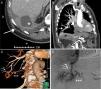

A) Imagen axial de la TC de abdomen en la que se observa una colección subfrénica derecha (asterisco). Nótese la presencia de cambios inflamatorios en el seno costofrénico derecho (flecha). B) Reconstrucción proyección de intensidad máxima (MIP) coronal de la angio-TC de tórax y abdomen superior en la que se visualiza una comunicación entre una arteria frénica inferior derecha hipertrófica (flecha negra) y una arteria subsegmentaria pulmonar del lóbulo inferior derecho (flecha blanca). C) Reconstrucción volumétrica (volume rendering) de la angio-TC de la fístula sistémico pulmonar (las flechas cortas señalan la arteria frénica inferior derecha mientras que las largas señalan la arteria pulmonar). D) Arteriografía en la que se visualiza el llenado retrógrado de las arterias pulmonares (flechas largas) desde la arteria frénica inferior derecha hipertrófica y tortuosa (flechas cortas).

Se trata de un varón de 79 años que consultó por episodios repetidos y autolimitados de hemoptisis, y que presentaba como antecedentes relevantes una colecistectomía laparoscópica que se complicó con un absceso subfrénico derecho (resuelto con drenaje y antibioterapia) 2 años antes (fig. 1A). Se descartó un origen de la hemoptisis en la vía aérea superior y el tracto digestivo mediante fibrobroncoscopia y endoscopia digestiva, pero en una tomografía computarizada (TC) de tórax con contraste se identificó una opacidad en el segmento postero-basal derecho que contactaba con la superficie diafragmática y presentaba, característicamente, vasos tortuosos a su alrededor. Ante estos hallazgos sospechosos de una malformación vascular se decidió realizar una angio-TC de tórax, la cual confirmó la existencia de una FSP entre una arteria frénica inferior derecha hipertrófica y una rama subsegmentaria de la arteria pulmonar del lóbulo inferior derecho (figs. 1B y C). Dicha FSP se trató mediante embolización selectiva con Onyx® (un copolímero de alcohol etileno-vinílico) de la aferencia arterial sistémica dependiente de la arteria frénica inferior derecha (fig. 1D). No se presentaron complicaciones posteriores ni se han evidenciado nuevos episodios de hemoptisis hasta el momento actual.